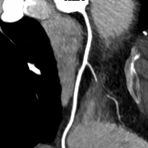

• Darstellung der Blutgefäße (sog. CT- Angiographie)

• Darstellung der großen Gefäße zur Erkennung von Gefäßverschlüssen (z. B. Mesenterial - Arterienembolie oder Einengungen von Gefäßen (z. B. Nierenarterien)

• Darstellung und Therapieplanung von Aneurysmen (CT- Angiographie)